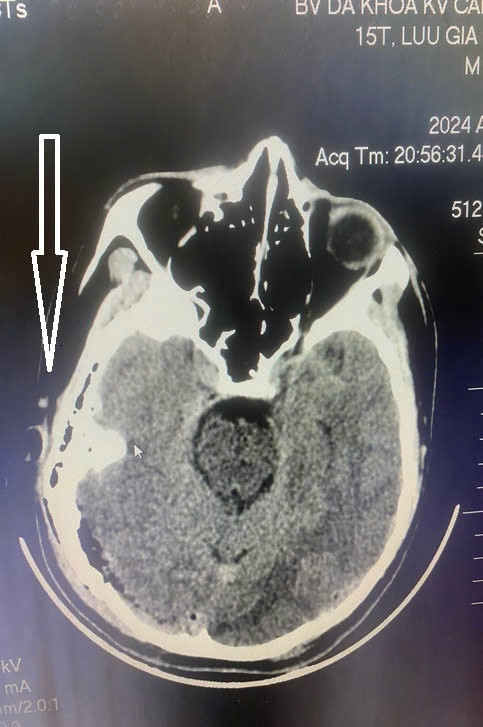

Các bác sĩ đã khám toàn trạng và làm các xét nghiệm cần thiết. Kết quả cho thấy bệnh nhân H có sưng nề biến dạng vùng thái dương phải; tay, chân, gối có nhiều vết xây xát. Hình ảnh chụp CT.Scanner cho thấy có tụ máu dưới và ngoài màng cứng vùng chẩm phải, xuất huyết rãnh liên bán cầu trước, vỡ xương trán – thái dương chẩm phải, vỡ xương đỉnh trái kèm tụ khí nội sọ rải rác. Bệnh nhân H. được sơ cấp cứu, giảm đau, chống phù não và chuyển lên Bệnh viện Đa khoa tỉnh để điều trị tiếp.

| Hình ảnh CTScanner sọ não của bệnh nhân H. cho thấy có tụ máu dưới và ngoài màng cứng vùng chẩm phải, xuất huyết rãnh liên bán cầu trước , vỡ xương trán –thái dương chẩm phải vỡ xương đỉnh trái kèm tụ khí nội sọ rải rác.. ẢNh BVCC |